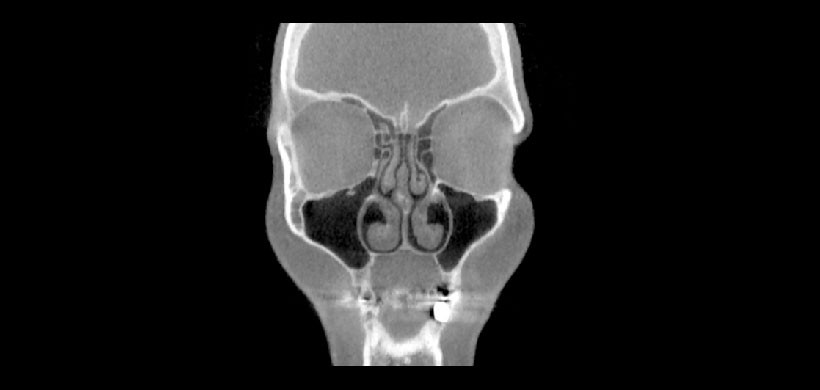

Fig 4. Tomografía volumétrica, vista coronal. Unión de la lámina cribosa y del proceso unciforme en un caso con concha bullosa ipsilateral.